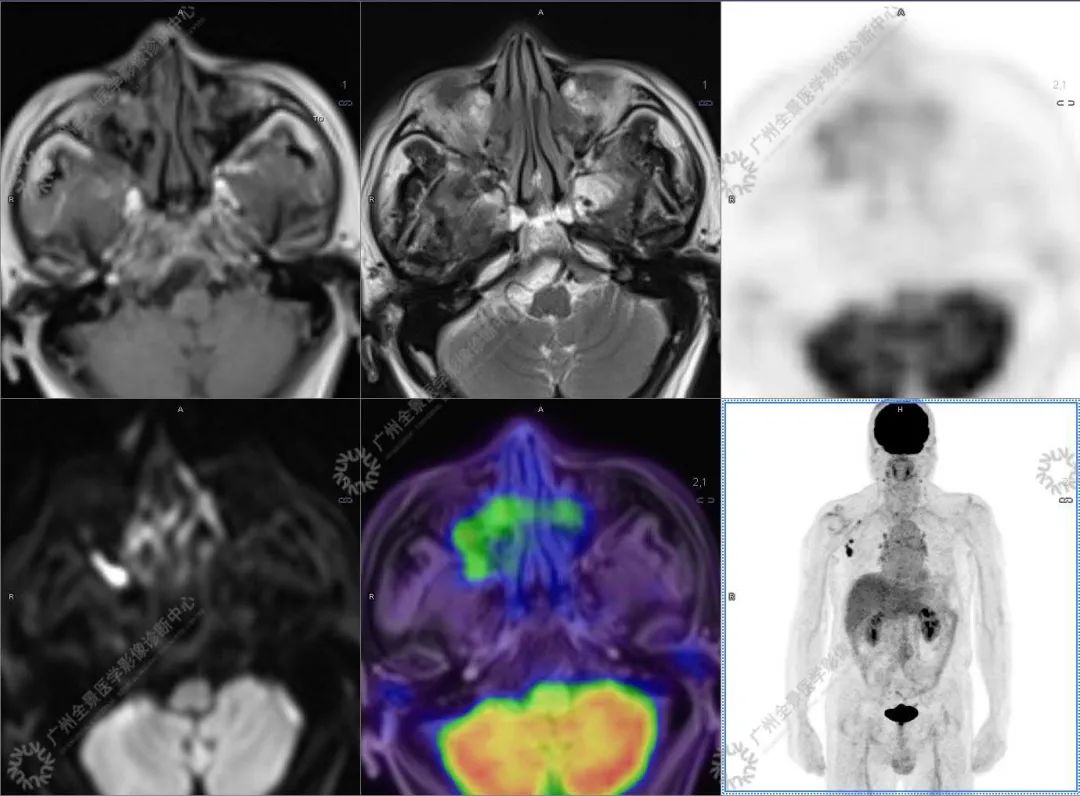

结合影像及实验室检查,临床最终考虑 IgG4 相关性疾病。

●18FDG-PET/CT 作为一种解剖和功能结合新的显像方法,IgG4-RD 的诊断及鉴别诊断中存在着巨大的优势:

●18FDG-PET/CT 扫描作为一种全身检查,有着传统影像学局部扫描无法比拟的优势,PET/CT 扫描不仅可以发现以临床症状为导向的局部病灶,更可以发现远隔部位的受累病灶。